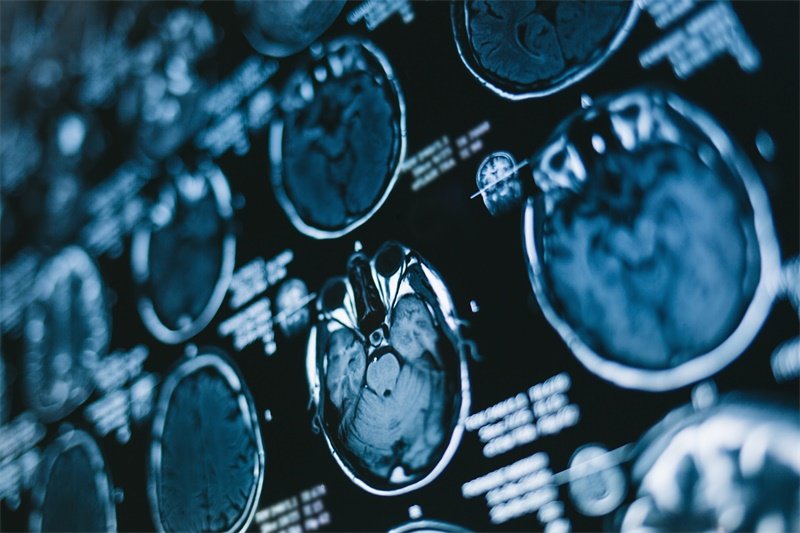

在MRI影像学检查中,前颅窝的占位性病变表现出不同的特征,影像学医生通过这些特征可以推测病变的性质。如:

占位性病变在MRI上的信号强度通常取决于它的组成和性质。良性病变,如腺瘤和囊肿,通常显示为低信号或等信号强度区域,而恶性病变则可能呈现高信号,尤其在T2加权成像中。在动态对比增强成像中,恶性病变的增强表现常常更为显著。

前颅窝的占位性病变通常可以通过其边界和形态来判断其性质。良性肿瘤如神经鞘瘤,通常呈现光滑边界及规则的轮廓;而恶性肿瘤则常有不规则边界及尚无明确分界。

在MRI影像中,前颅窝占位性病变的位置及其与邻近结构的关系也起着重要的诊断作用。例如,浸润性肿瘤如胶质瘤往往在结构上表现为与周围组织难以分离,而外生性肿瘤则可能更易于界定。